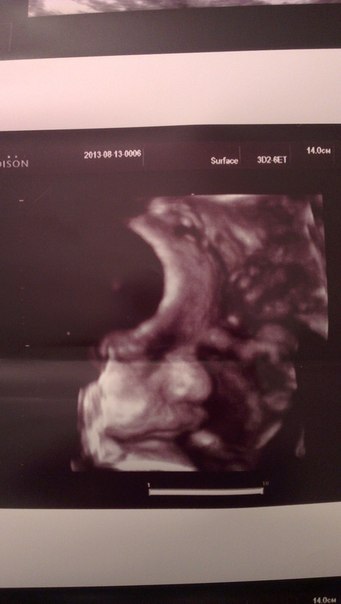

наше узи в 32 полных недель)

УЗИ, КТГ, доплерэмоции просто переполняют! хотели пойти с мужем и посмотреть в 3D,но из-за работы у него не получилось(( врач просто обалденная! очень жалею,что предыдущие узи сделала не у нее,но я решила еще перед родами сходить к ней,т.к у ребеночка однократное обвитие вокруг шеи,мы послушали кровоотток,вроде все хорошо,и гиня и узистка сказали,что это у всех бывает,что еще размотается. Ребеночек лежит головкой вниз,воды в норме,плацунта уже 2 степени зрелости,зев закрыт,толщина плаценты 33 мм,длина шейки 26 мм,плацента высоко,сердечко 148т ударов в минуту,мне дали его послушать!! о Боже,как это прекрасно!!

пальчики считали,пяточки смотрели,сердечко четырехкамерное,все шикарно врач сказала,весим мы уже 2100 гр! Иииии,у нас сыночек,как и предположили в 12 недель!